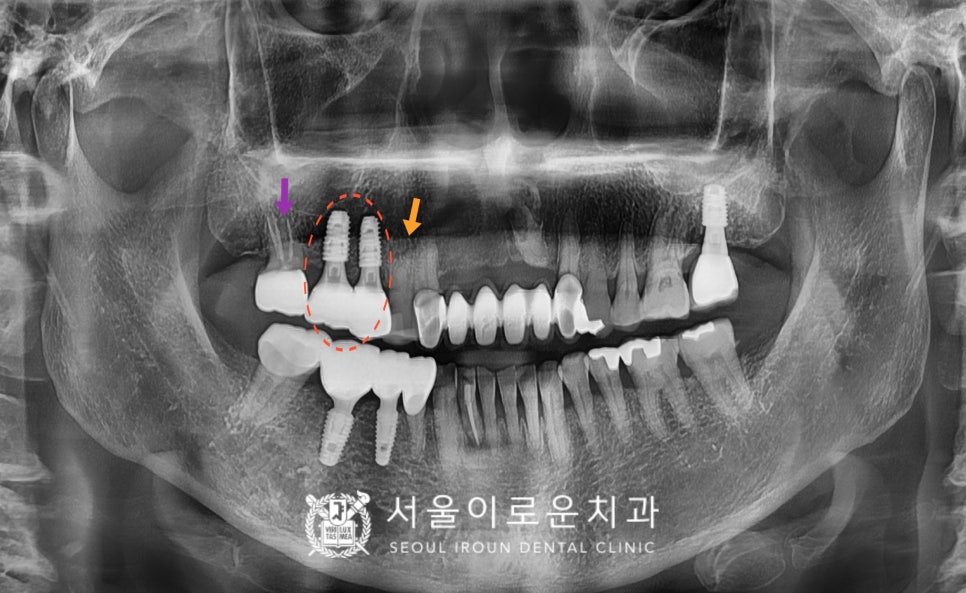

우선 위턱 두 번째 작은 어금니(#15)를

발치하였고,

기존 상실된 부위와 함께

즉시 임플란트 식립을 진행하였습니다.

임플란트 즉시 식립은

누구나 가능한 것은 아닙니다.

기본적으로 잇몸뼈가 건강해야 되고

의료진의 정밀한 검사를 통한

진.단하에 가능한데요.

환.자분의 경우 연세에 비해

잇몸뼈도 건강하였고,

위턱 어금니 임플란트 시

가장 고려해할 상악동 막도

가까이 내려와 있지 않아

잔존 잇몸뼈가 충분하였기 때문에

임플란트 즉시 식립이 가능했습니다.

그리고 임플란트 식립 3개월 후

osstell beacon이라는 골 유착을

확인할 수 있는 장비를 이용하여

isq 측정해주었습니다.

잇몸뼈와 임플란트가

잘 결합되었다는 안정 값을 확인한 뒤

임플란트 보철물 제작을 위한

인상채득을 진행하였습니다.